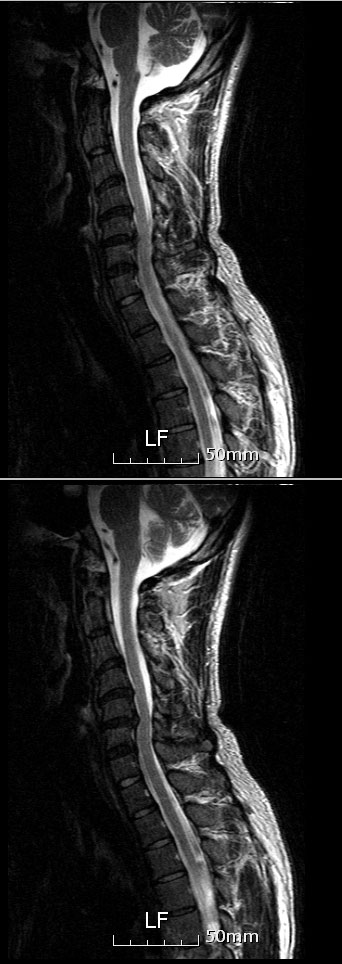

(ֹȣ : 27416348fe74 / ī,ͳݹŷ ιȣ : 80862609) Խ ȣϽ 1C~7C شǴ () ºҷ Ÿ ֽϴ. 2C.پ˷⼺(˷) 3C., 3C.帧, 4C., 5C.ٸ, 6C.ڸ , 6C.ھ Ḳ , 6C.ڻ , 6C., 5T.ȯ ҷ, 9T.˷, 10T.ٸǷ, 11T.ٳġ 帧, 12T.ٰ (), 1L., 1L., 3L. 4L Һ Һ, 4L. 财, 5L.ڹ ٸ ȯ, ߸, ߺ ༺ ũ, ߵũ(߰), ߺ ô, ߺ ô, ǥغ Ͻô Ͽ ߰ մϴ. Ͽ ũ(߰Ż), ũ(߰Ż)ġ, ȱ ǰϰų ڸ, , ڰ , , Ҹ ġ ߷, , нɷ Ʈ 氨 ͳ ˻ڷ õ mri ũ 3c 4c 5c 6c ̻Ұ Ű洭 Ұ ߸ ڸ ϰ ڿ.. ߶ ʰ ħ ļ ѳ 2-3 ϰ ..ٸ |